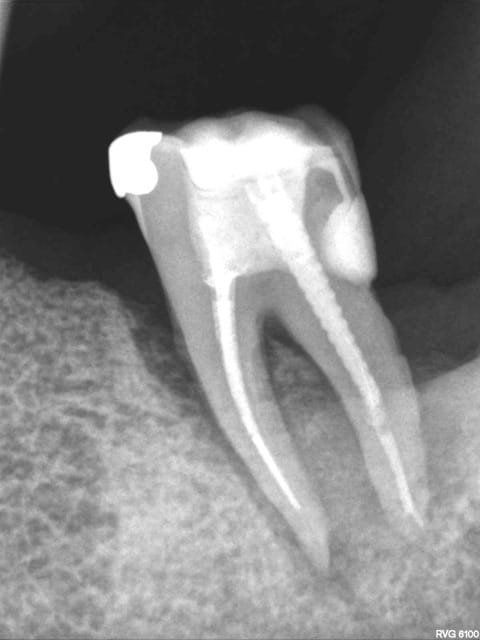

Petite présentation rx pour savoir ce que vous pensez de ce cas. R26 = 14/10/2010

R 52 = 07/02/2011

R 69 = 11/05/2013

R71 est de cette semaine, allez y comprendre quelque chose, dame nature a été très gentille sur ce coup là, de l'os s'est reformé.

Une explication à me proposer?